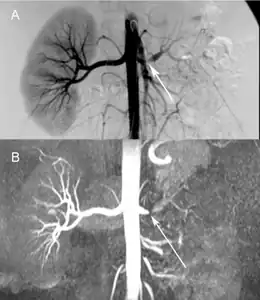

Comparison a) Digital subtraction arteriography and b) Unenhanced Magnetic resonance angiography of suboclusive left renal artery stenosis arrows